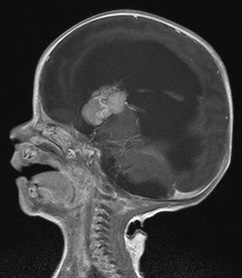

复查的头颅MRI检查提示孩子右侧脑室内占位性病变并交通性脑积水、间质性脑水肿,颅内硬膜下出血,增强扫描检查提示肿瘤病变均匀强化,肿瘤血供丰富(如下图)。